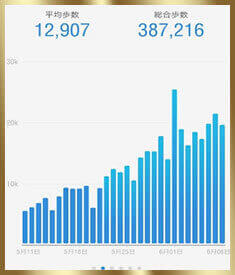

1日2万歩以上歩けるまでに回復!

2万歩以上歩けるように!